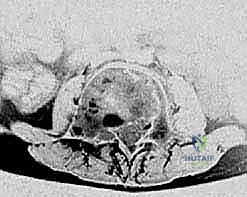

في الـ ABC، تظهر الآفة غير مركزية، متمددة، وتدفع قشرة العظم للخارج لتصبح رقيقة جداً مثل "قشرة البيضة".

تُظهر هذه الأشعة السينية كيس عظم متمدد (ABC). لاحظ التوسع الكبير في العظم وترقق القشرة العظمية مقارنة بالكيس أحادي الغرفة.

صور الرنين المغناطيسي والأشعة المقطعية المتطورة توضح "مستويات السائل-السائل" المميزة لكيس العظم المتمدد، بالإضافة إلى التخطيط الدقيق لحدود الآفة قبل التدخل الجراحي.